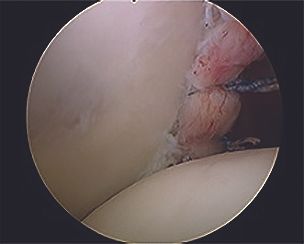

1. Arthroscopic capsulolabral repair (arthroscopic posterior Bankart)

This technique is indicated when the only damage is posterior labral detachment (Fig. 3) with no significant bone lesions. The posterior labrum can be reinserted by using anchors (Fig. 4), but posterior capsule tensioning [4] is crucial in order to recreate the glenoid concavity and restore the constraints from the capsuloligamentous structures.